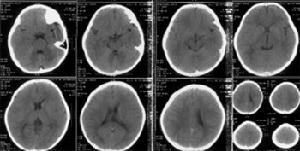

智慧型低下腦部片智力低下者軀體體徵及神經系統障礙常常不明顯,但不數較明顯。常見的軀體體徵有:大頭、小頭、塔狀頭、尖頭、眼距增寬、髮際低、面部兩側不對稱。外耳鼻上齶發育異常。四肢、手足、脊柱畸形,皮膚紋理異常。部分患者伴有癲癇及神經系統體徵。